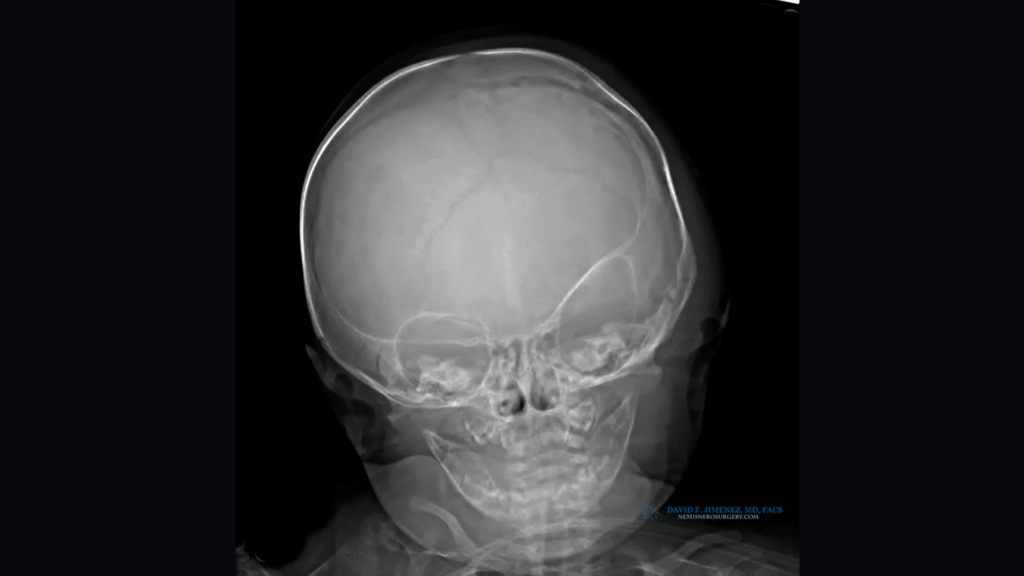

Endoscopic-assisted craniosynostosis surgery is a minimally invasive technique developed to treat infants diagnosed within the first few months of life. Introduced more than two decades ago, this approach allows for safe and early correction of abnormal skull growth by releasing the fused suture through small incisions.

The principle behind the endoscopic method is to use the natural, rapid growth of the infant brain to reshape the skull once the restriction is released. Because the incisions are small and the bone removal limited, this method reduces surgical time, blood loss, swelling, and hospital stay compared to open cranial vault reconstruction.